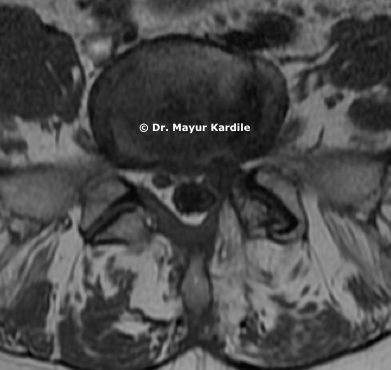

Cervical Myelopathy

65 yr gentleman